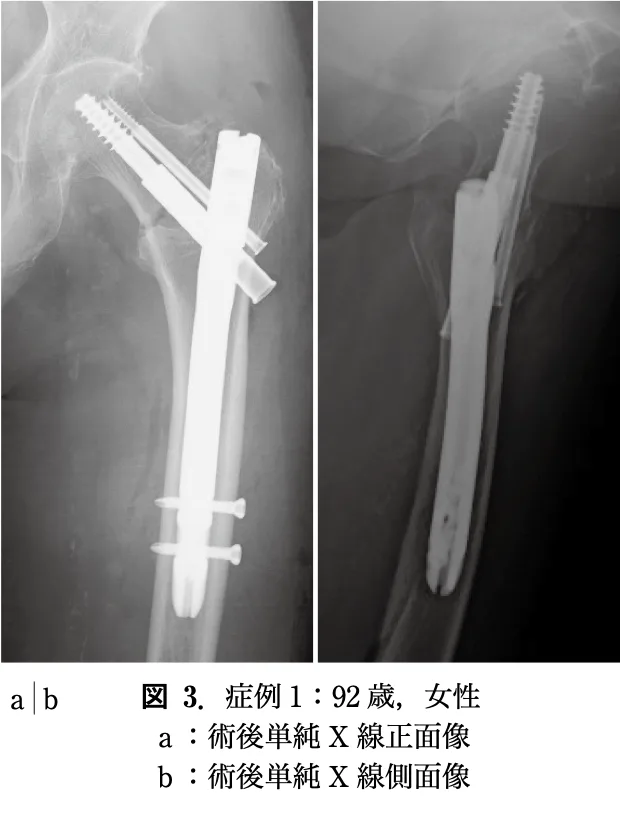

引用元:川田紘己. 大腿骨転子部骨折に対するZNN CM Fortisネイルを使用したanterior support screw (AS2)の挿入の検討. 骨折. 2023. 45.

13時半から, 大腿骨転子部骨折の超高齢患者さんに対する骨接合術を執刀.

予定通り, 40分ほどで終了しました.